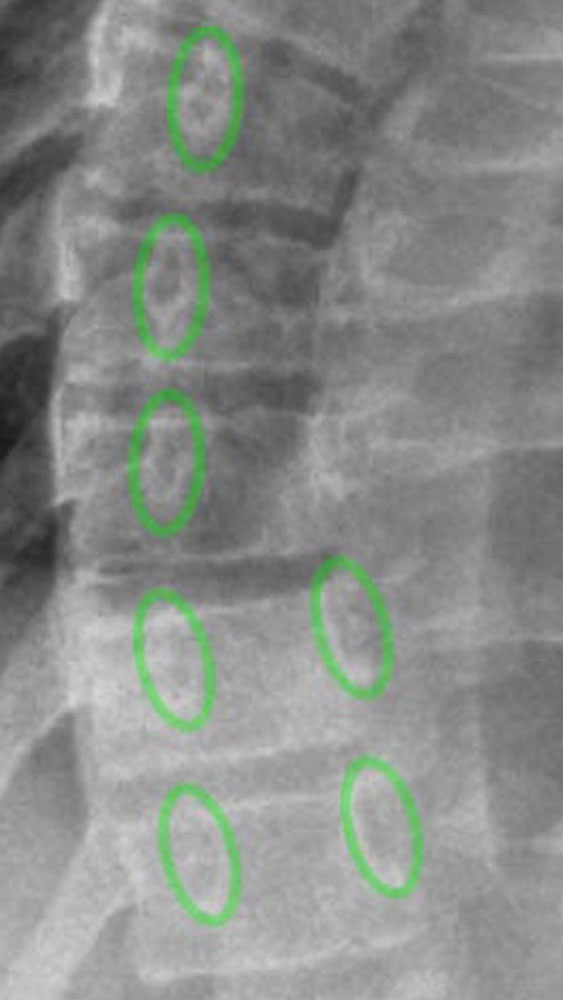

The radiograph must be taken in a standing position and usually as a posterior-anterior image of the entire spine on a composed X-ray (one image, whole spine).

Here, the Cobb angle, the rib angle, and the rotation of the vertebral bodies are assessed.

In addition, to analyze the prognosis of the future progression of the scoliosis, the expected spinal growth can be calculated with the aid of assessment of the iliac crest apophysis (so-called Risser stage). In this case, the iliac crest should additionally be imaged on the whole-spine radiograph.